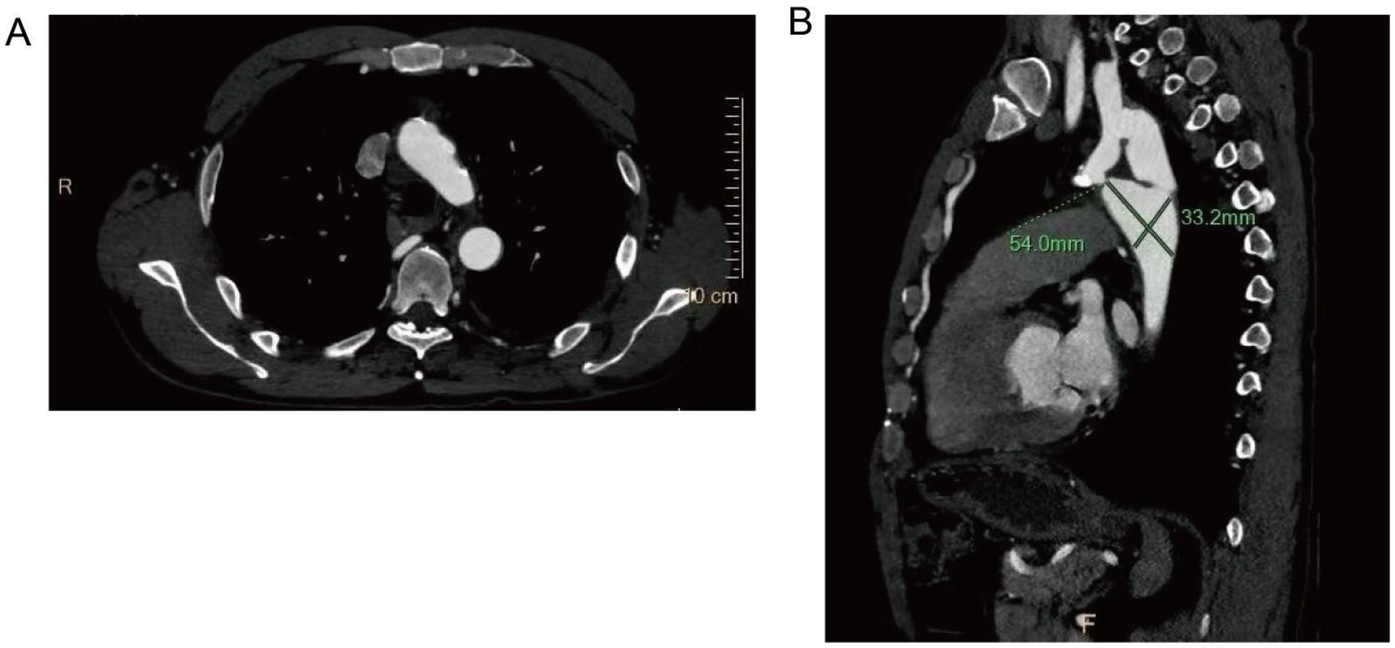

Further evaluation using computed tomography angiography (CTA) confirmed severe CoA, with near-complete interruption of the descending aorta at the isthmus and extensive collateral circulation, including prominently dilated and tortuous internal thoracic arteries (Figure 1). The renal arteries were assessed and found to be unremarkable, with preserved renal function throughout hospitalization.

Figure 1

Preoperative computed tomography angiography (CTA) findings. (A) Severe narrowing at the aortic isthmus (“sandglass-shaped” coarctation, arrow); (B, C) Markedly dilated and tortuous paravertebral arteries, demonstrating extensive collateral circulation; (D) Prominent internal thoracic arteries serving as major collateral pathways.